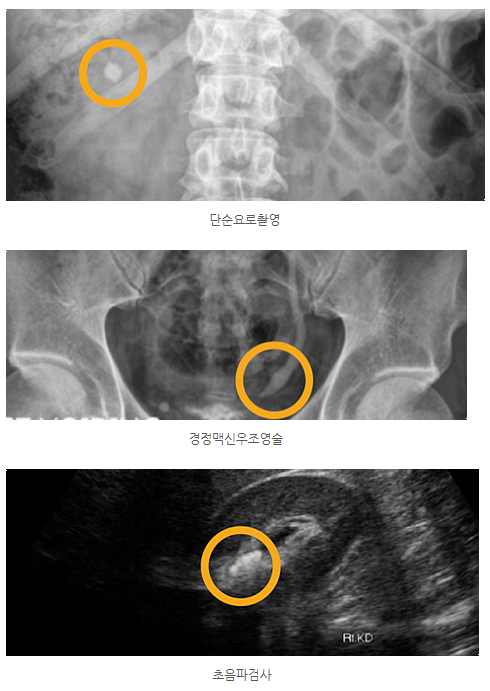

요로결석은 환자의 증상과 신체검사, 소변 검사, 단순요로촬영, 경정맥신우조영술, 초음파 검사 등을 통해 진단하게 됩니다.

결석의 위치는 단순요로촬영을 통해 확인하거나 경정맥신우조영술로 결석이 요관의 어떤 부위를 막고 있는지를 확인할 수 있습니다. X-레이로 요석이 확인되지 않으면 초음파 검사로 간단하게 확인하는 방법도 있습니다.